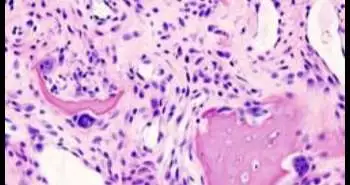

По словам исследователей, математическое моделирование позволило выявить два различных паттерна активности остеоартрита. В рамках своей работы они изучили биологические образцы 60 пациентов с артритом коленного сустава и экспрессируемые их тканями гены.